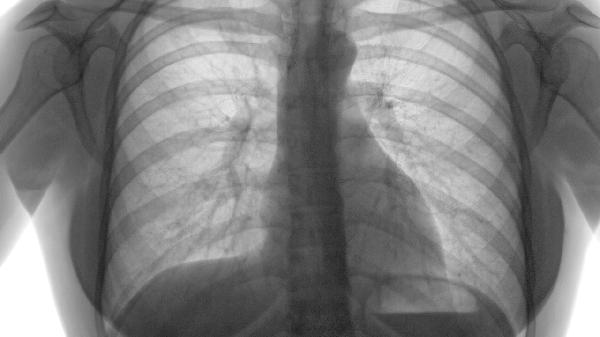

长期肺过度充气导致胸廓前后径增大,形成特征性桶状胸。这是肺组织弹性丧失的体征,需通过肺功能检查确诊。这种情况需长期使用沙美特罗替卡松复合制剂延缓病情进展。